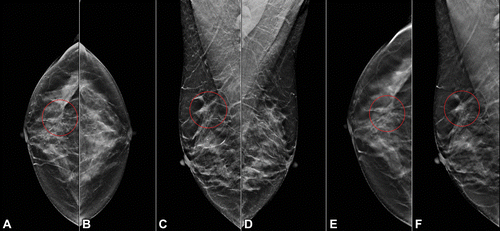

In a retrospective study involving 4,310 women and a total of 5,182 digital breast tomosynthesis (DBT) procedures, the authors found that utilization of an AI model to filter out normal DBT exams led to a 39.6 percent reduction in workload, similar sensitivity for detecting breast cancer (90.0 percent compared to 90.8 percent for radiologist-led screenings) and a 25 percent lower recall rate (6.9 percent compared to 9.2 percent for radiologists).

Researchers described the AI model as a mixture of 45 deep learning classifiers that processed the DBT views and five machine learning classifiers that processed clinical information. According to the study, researchers deemed a DBT exam positive or negative for cancer if there were corresponding biopsy findings within 12 months after the DBT exam.